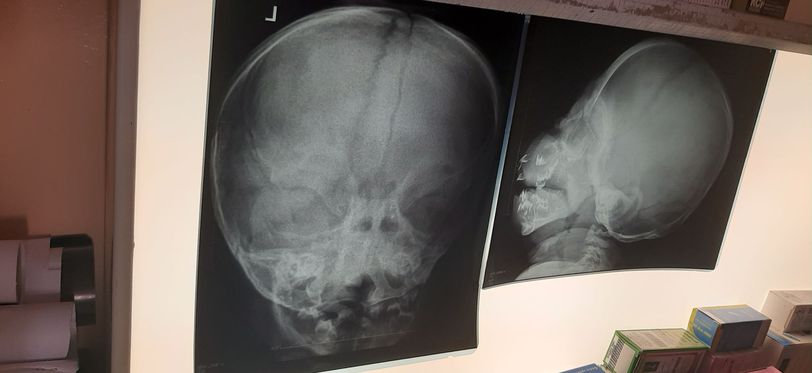

Juvenile hayline fibramatosis

9 months years old male patient with gingival hypertrophy and multiple nodules over the body